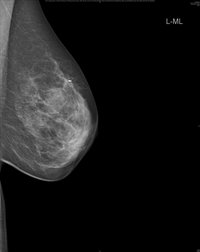

488. Brustkrebs-OP nach Chemotherapie noch nötig? Künstliche Intelligenz soll Diagnostik unterstützen

Datum: 2021-02-03

Mammographie - Responder Studie, Quelle: Universitätsklinikum Heidelberg (UKHD) Pressemitteilung des Universitätsklinikums Heidelberg (UKHD)